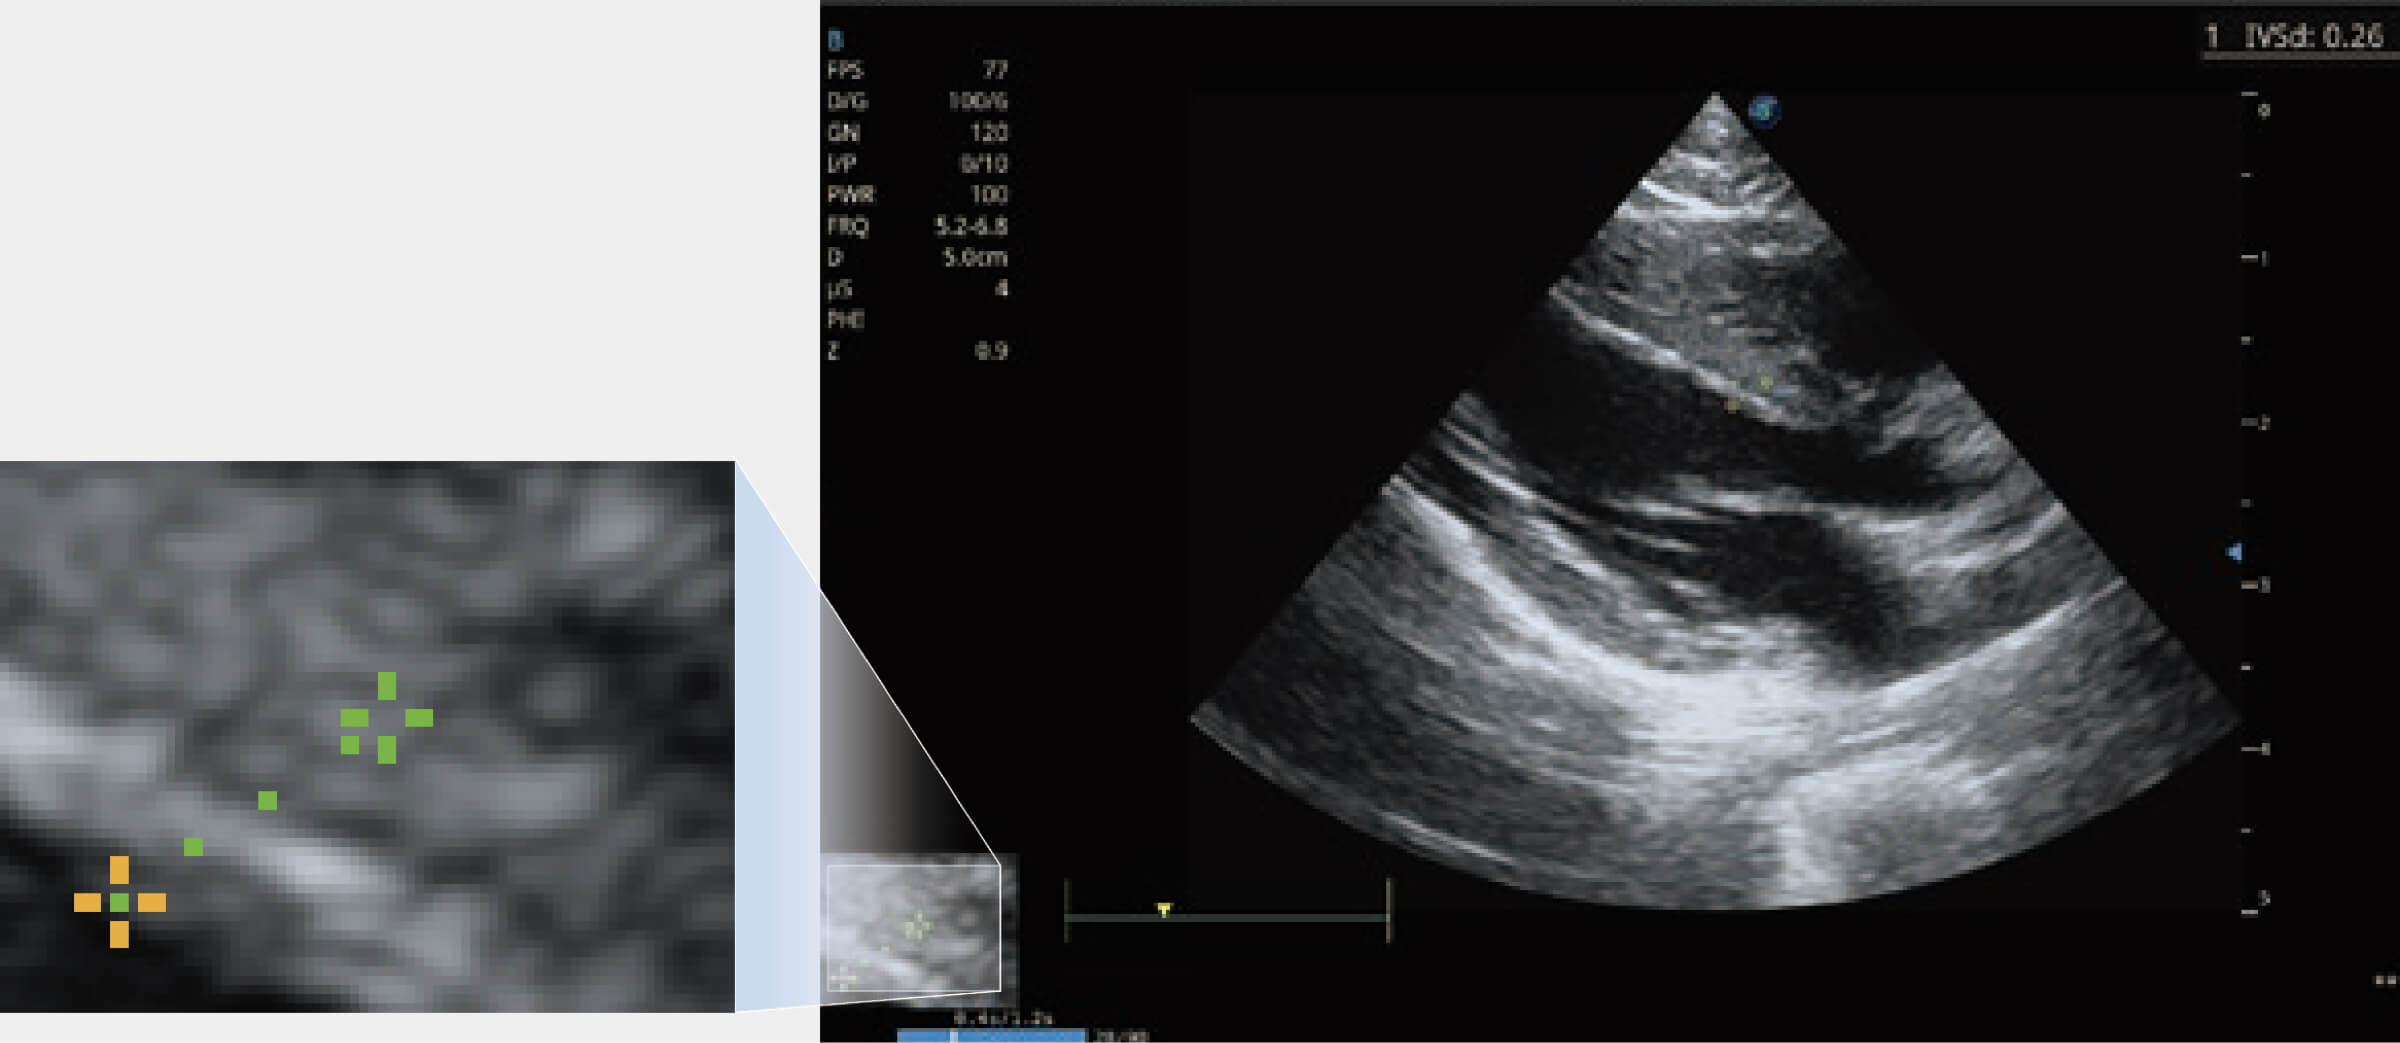

通過(guò)360度任意調(diào)節(jié)3條M型取樣線,在同一心動(dòng)周期上觀察心臟不同位置的運(yùn)動(dòng)曲線,得到準(zhǔn)確的心功能測(cè)量數(shù)據(jù),有效評(píng)估心肌運(yùn)動(dòng)及左心室功能。

實(shí)時(shí)用顏色表示心肌組織運(yùn)動(dòng),觀察和定量組織的運(yùn)動(dòng)情況,對(duì)快速檢測(cè)與評(píng)估心肌的灌注和活性、電傳導(dǎo)及心肌收縮和舒張功能等均能提供重要的診斷信息。